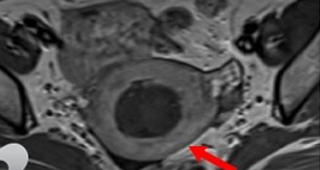

자궁선근증 비수술 하이푸 치료 후 임신사례입니다.하이푸 시술전 MRI 사진상 자궁은 6cm 크기로 심하게 후굴되어 있으며 자궁후벽을 중심으로 자궁선근증변화 소견이 관찰됩니다. 아래의 MRI 사진은 자궁선근증 하이푸...